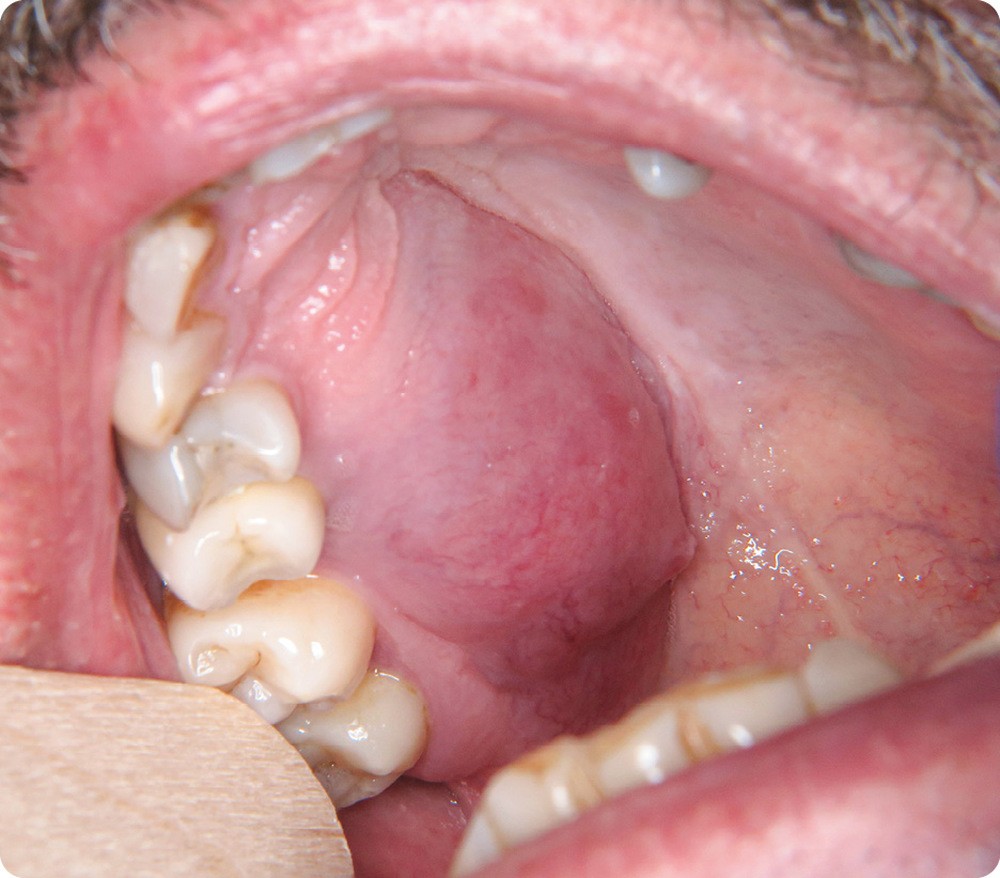

- On observait une tuméfaction oblongue, étendue sur l’hémi-maxillaire droit de 13 à 17, côté palatin. à la palpation, la lésion était rénitente.